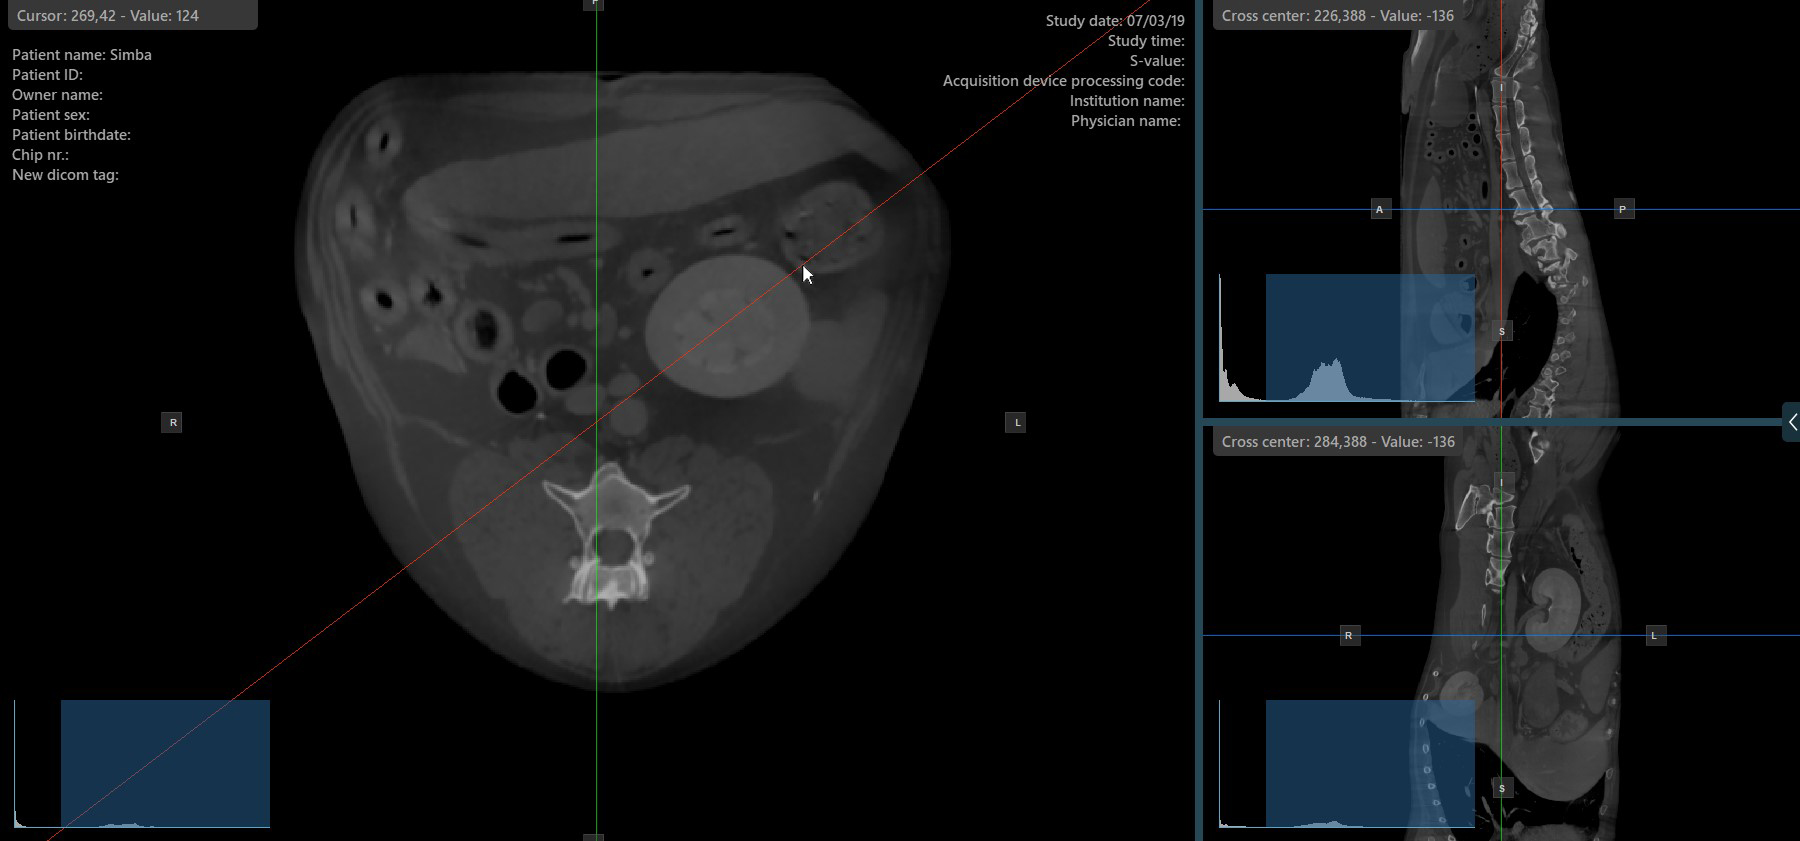

Press the Perpendicular Slicers icon in the left toolbar to activate simultaneous rotation of the slicers. Regardless of their previous orientation, the slicers are repositioned to be perpendicular to each other.

Toggle the Perpendicular Slicers option to switch the active mode of the slicers at any time, or choose one of the Tools -> Perpendicular Slicers or Tools -> Separate Slicers options from the CT Viewer menu.